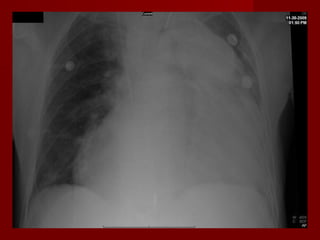

    Chest Radiograph:

1.   Enlarged pulmonary artery.

2.   Enlarged right ventricle.

3.   Distended azygous or other central vein.

4.   Westermark sign “oligemia of lung lobe or

entire lung “.

5.   Hampton’s hump “wedge shaped opacity

6.   COPD signs as anterior-posterior diameter ,

flattening of diaphragm , honeycombing and

hyperlucency.

Investigations Help InDiagnosis  Chest Radiograph: 1. Enlarged pulmonary artery. 2. Enlarged right ventricle. 3. Distended azygous or other central vein. 4. Westermark sign “oligemia of lung lobe or entire lung “. 5. Hampton’s hump “wedge shaped opacity 6. COPD signs as anterior-posterior diameter , flattening of diaphragm , honeycombing and hyperlucency.